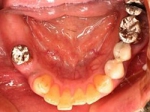

両側5歯症例 主訴-義歯のバネが壊れて手前の歯が痛んできた。 術前(旧義歯装着、鏡像)